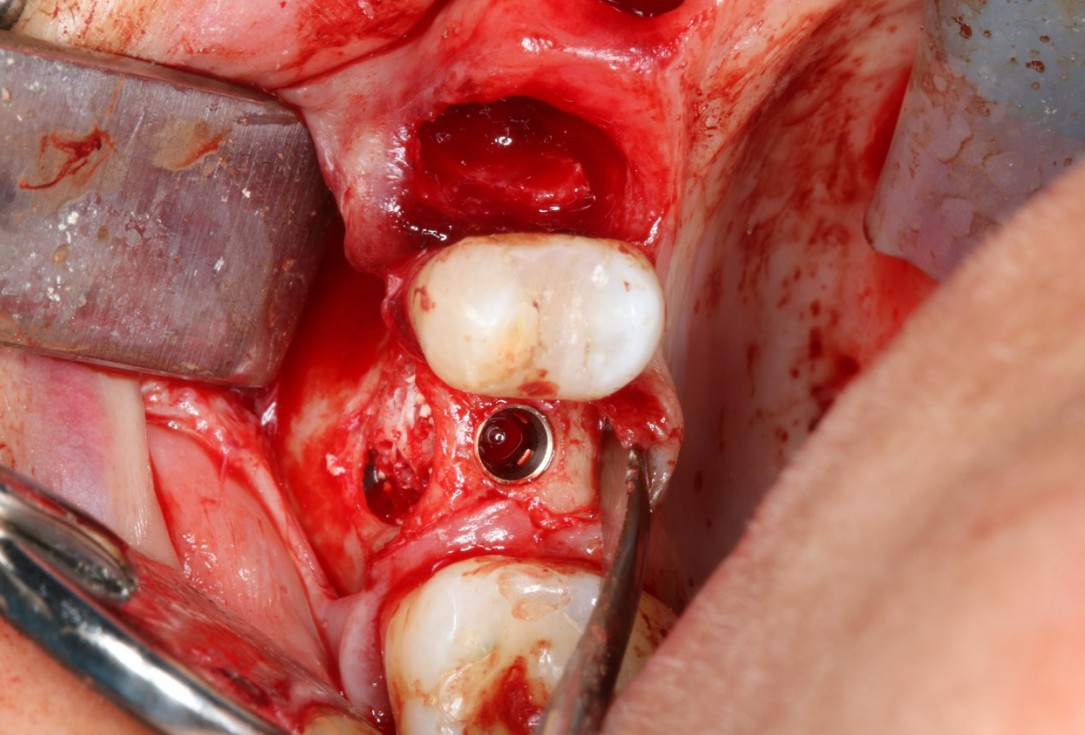

Periimplantitis treatment with maxgraft® bonering - Dr. B. Giesenhagen

Severe periimplantitis at tooth 15 with bone loss up to 1/3 of the implant